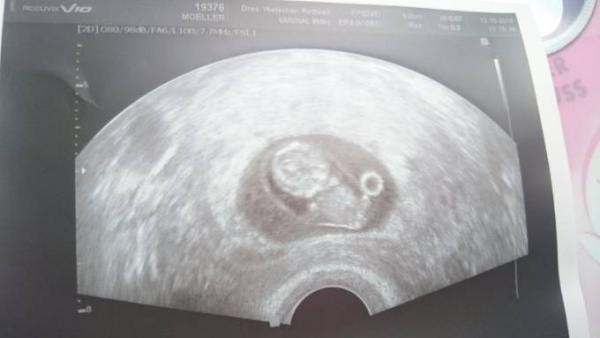

Hallo. Ich war damals bei 9+1 beim Frauenarzt und mein kleiner hatte da eine ssl von 2,21 cm. Aber arme und Beine waren zu erkennen, zumindest so halb :D Anbei ein Foto vom Ultraschallbild. Aber das kann sich auf ein paar Tage alles entwickeln.. ich denke wenn deine fä schreibt zeitgerechte Entwicklung, dann passt sicher alles :)